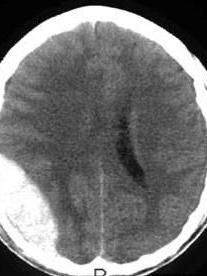

輔助檢查:1、超聲檢查:超音波探查,血腫多位於大腦半球的一側,可見腦中線波向對側明顯偏移。2、顱骨X線片,硬膜外血腫伴有顱骨骨折者占95%,且絕大多數發生在著力部位,無骨折者少見,當骨折線過腦膜中動脈溝或靜脈竇溝時,多可考慮硬膜外血腫的可能。3、腦血管造影 通過數字減影像的正位和側位進行觀察。典型的硬腦膜外血腫可顯示為雙凸鏡形無血管區及周邊血管受壓征。矢狀竇(或橫竇)旁或跨竇的硬膜外血腫,在靜脈期可見上靜脈竇及注入靜脈顯影,並見血管受壓移位。於傷後數小時造影者,有時可見造影劑外滲。4、CT掃描 頭顱CT掃描最重要的是能清晰地顯示血腫的部位、大小及合併腦損傷的程度等。且可連續、動態地觀察血腫的變化。CT掃描片上,於顱骨內板下方,急性血腫為梭形或半月形高密度影,CT值40-100Hu,密度均勻,邊界清楚,亞急性血腫為雙凸面鏡高密度影,系混雜密度。均有同側側腦室受壓,中線結構向對側移位。骨窗像上,能顯示顱骨骨折。5、MRI掃描 在MR圖像上血腫形態與CT掃描表現上基本相似,能分辨出低信號的硬膜,不同時期的血腫在T1、T2像上表現不同。